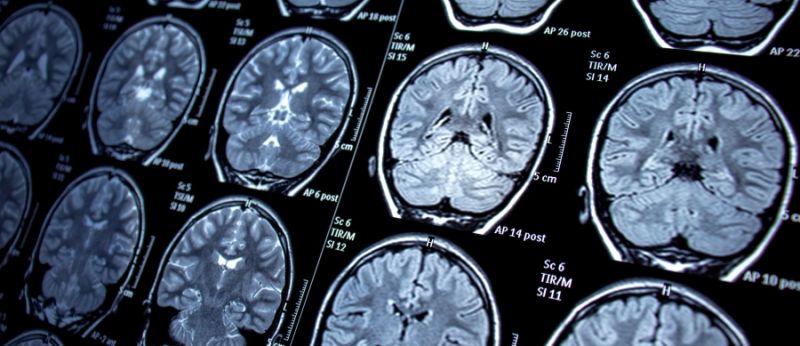

O relato descreve o caso de um homem de 28 anos diagnosticado com deficiência do transportador de creatina (CRTR-D), uma condição genética rara que compromete o transporte de creatina, uma substância vital para a produção de energia nas células, especialmente em músculos e neurônios. A ausência dessa transportadora leva a uma série de problemas de saúde, incluindo dificuldades relacionadas ao sistema nervoso e ao desenvolvimento muscular.

A deficiência do transportador de creatina (CRTR-D) é uma condição genética rara ligada ao cromossomo X, pertencente ao grupo de distúrbios cerebrais causados pela falta de creatina. As principais manifestações incluem atraso no desenvolvimento e a ocorrência de epilepsia. Até o momento, menos de 200 casos foram documentados, o que resulta em opções limitadas de tratamento. Os tratamentos disponíveis, predominantemente precursores da creatina, apresentam efeitos restritos na progressão da doença. Em relação à epilepsia, o tratamento convencional muitas vezes não é eficaz em casos refratários.